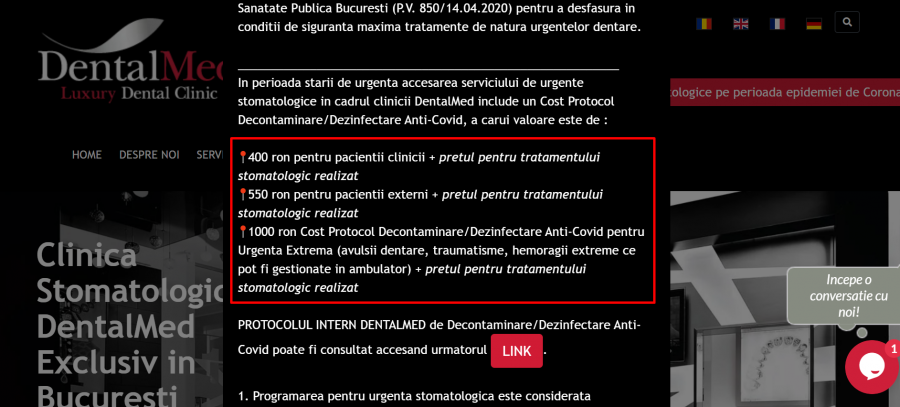

În timp ce instituțiile publice înaintau hârtii și cereri dintr-o parte în alte, cabinetele stomatologice de apartament adunau tot mai multe pierderi și niciun câștig. Pe de altă parte, cele șase care și-au permis cumpărarea sau închirierea unui nebulizator scoteau sute de lei în plus din buzunarul pacientului. De exemplu, Dental Med a inclus, pe lângă prețul standard al unei proceduri, un cost pentru protocolul de decontaminare anti-covid cuprins între 400 și 1000 lei. Există și clinici cu adaosuri mai mici, precum Trident, cu 200 de lei, sau Kopfzeit, cu 150 lei.